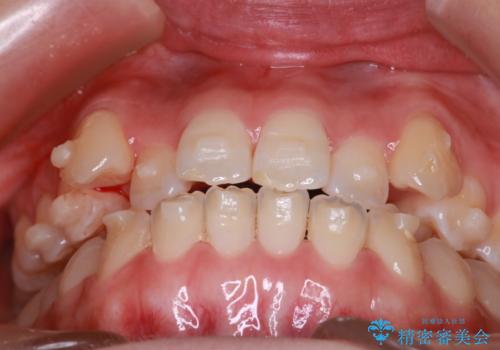

MARPEで非抜歯矯正|オープンバイトと八重歯を改善

- 治療計画

上顎にTAD(矯正用アンカースクリュー)を設置し、MARPEにより骨格レベルで上顎の幅を拡大。数週間の拡大期間を経て十分なスペースを確保したのち、マウスピース型矯正装置(インビザライン)で歯列全体を整えました。八重歯もアーチ内に自然に収まり、非抜歯で審美性と機能性を両立。治療後は「噛み合わせが安定して笑顔に自信が持てるようになった」とご本人にも大変満足していただきました。